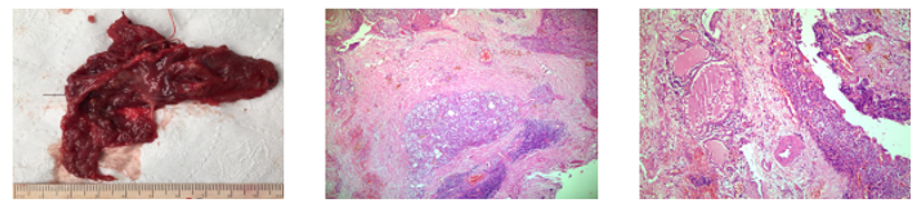

A right thyroid lobectomy and isthmusectomy were performed (Figure 2) without complications. The patient's progress in the ward was good, with immediate postoperative PTH of 196 pg/ml. Pathological examination confirmed the presence of intrathyroidal carcinoma with angioinvasion (Figure 3) pT1a.

Pathological anatomy (Figure 4): Parathyroid carcinoma infiltrating contiguous soft tissues and adjacent thyroid parenchyma. pT2. Associated with an encapsulated papillary microcarcinoma (microscopic finding) at the isthmus level. pT1a

The pathological diagnosis responds to the criteria of Schantz and Castleman: 1) organization in a solid structure and with a trabecular pattern (90% of cases), 2) mitotic figures in the parenchymal cells (81%), 3) capsular invasion (67%) and 4) invasion of blood vessels (12%)11 The presence of infiltration of adjacent structures, vascular invasion, of extraparathyroid vessels, as well as the presence of metastases are definitive elements of malignancy.